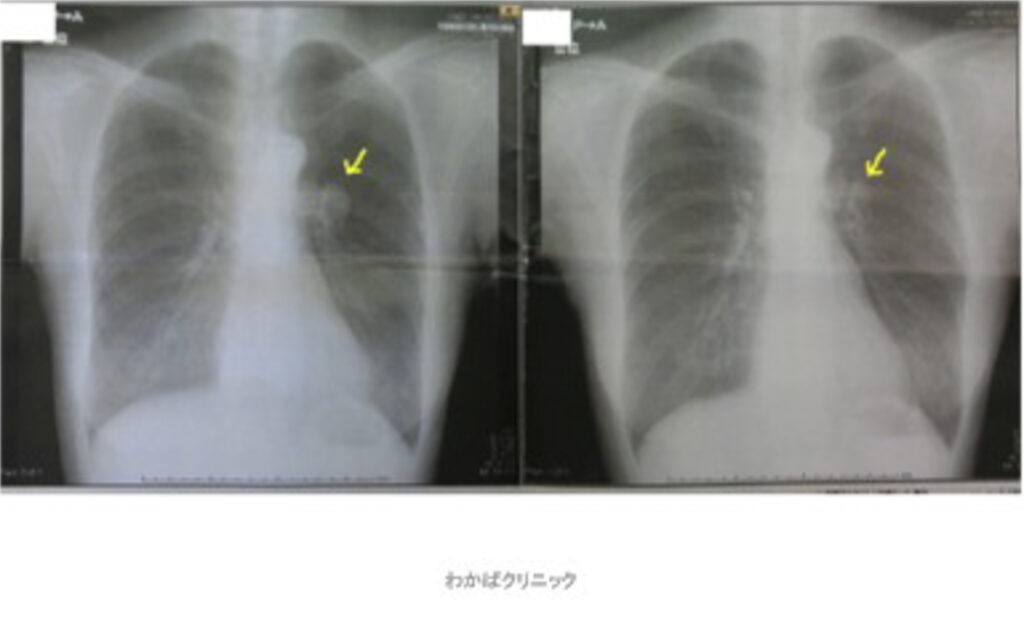

- 西洋医学的な効果判定(必ず必要です)

- CT・MRI・超音波検査 他